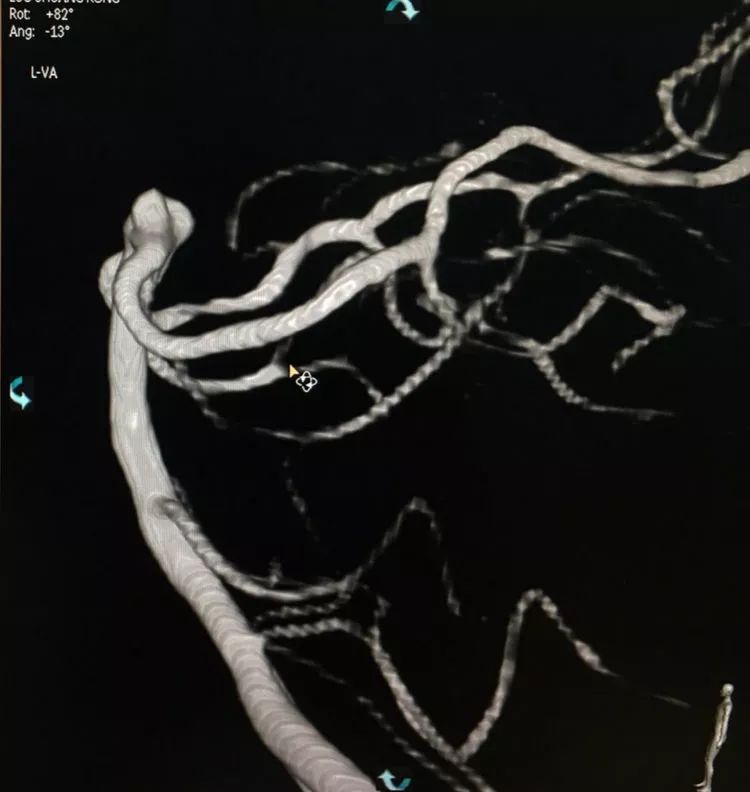

患者女性,80岁,以SAH于2017.5.20急诊入院,CTA示基底动脉顶端动脉瘤。

左椎动脉造影三维重建和测量